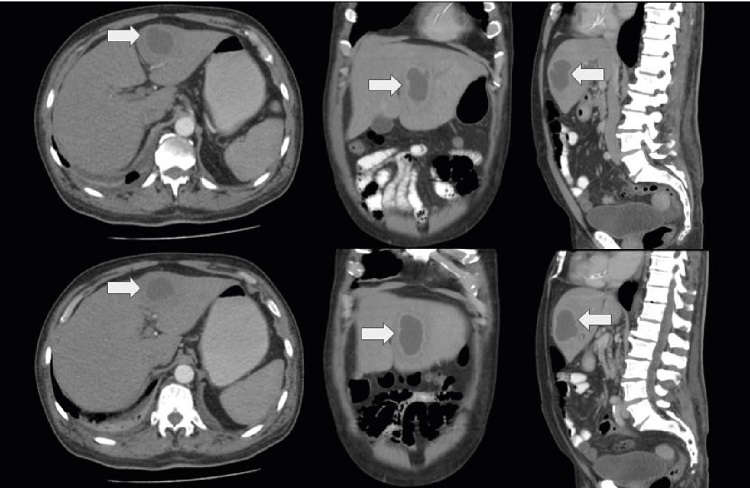

Hepatobiliary ultrasound showed an abscess of 73 x 62 mm in segment IV; the bile duct and pancreas were within normal limits. To better characterize the lesion evidenced in the liver, a contrast-enhanced computed tomography of the abdomen was performed (figure 1). The patient was referred for percutaneous drainage of the abscess under ultrasound and fluoroscopic guidance which was done with minimal difficulty, and the drained material was cultured.

In this clinical case, the report of the microbiological isolation of G. adiacens is presented in a patient with no pathological history or user of devices that facilitate its colonization. The patient presented hypotension, leukocytosis, positive cultures, and the tomography showed a liver abscess. Currently, more than 90% of abscesses are polymicrobial 4, while in our case only G. adiacens was detected as the main pathogen 5.